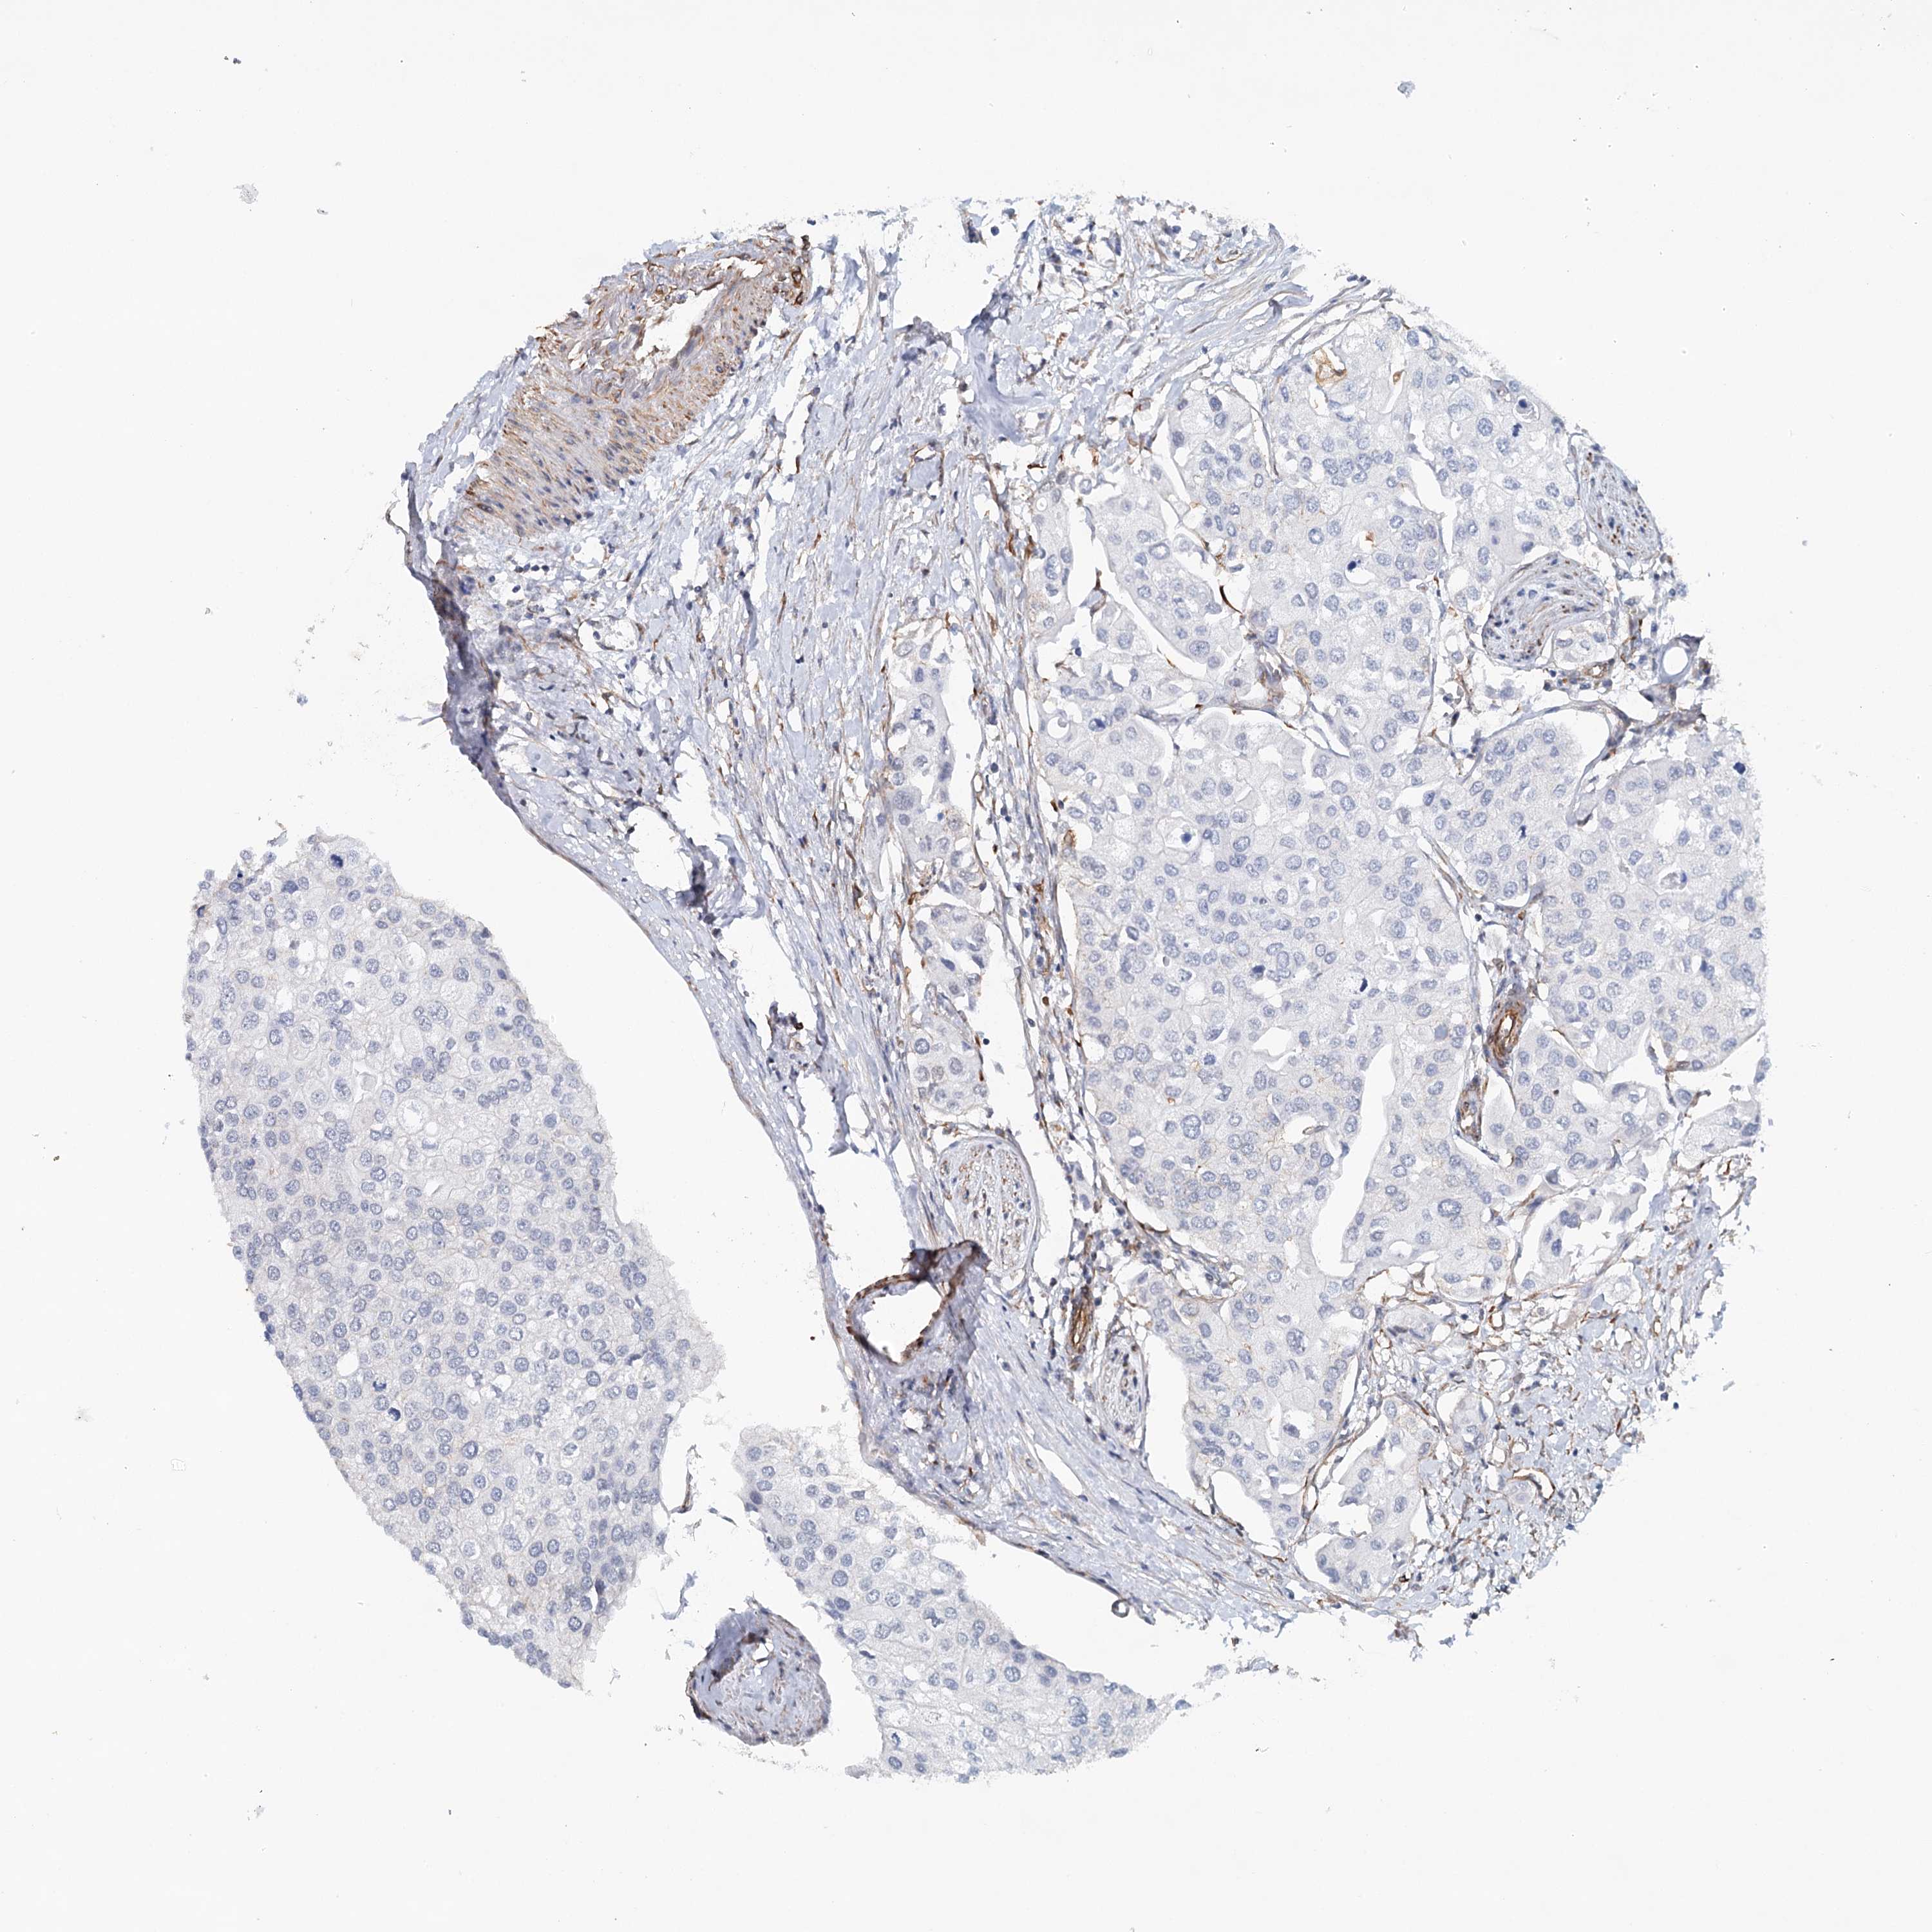

UROTHELIAL CANCER - Protein expressioni

A mouse-over function shows sample information and annotation data. Click on an image to view it in a full screen mode. Samples can be filtered based on level of antibody staining by selecting one or several of the following categories: high, medium, low and not detected. The assay and annotation is described here.

Note that samples used for immunohistochemistry by the Human Protein Atlas do not correspond to samples in the TCGA dataset.

Antibody stainingi

Antibody staining in the annotated cell types in the current human tissue is reported as not detected, low, medium, or high, based on conventional immunohistochemistry profiling in selected tissues. This score is based on the combination of the staining intensity and fraction of stained cells.

Each image is clickable and will lead to virtual microscopy that enables deeper exploration of all samples and also displays staining intensity scores, fraction scores and subcellular localization as well as patient and tissue information for each sample.

Antibody CAB033265

Urothelial carcinoma, High grade

Urothelial carcinoma, Low grade

Urothelial carcinoma, NOS